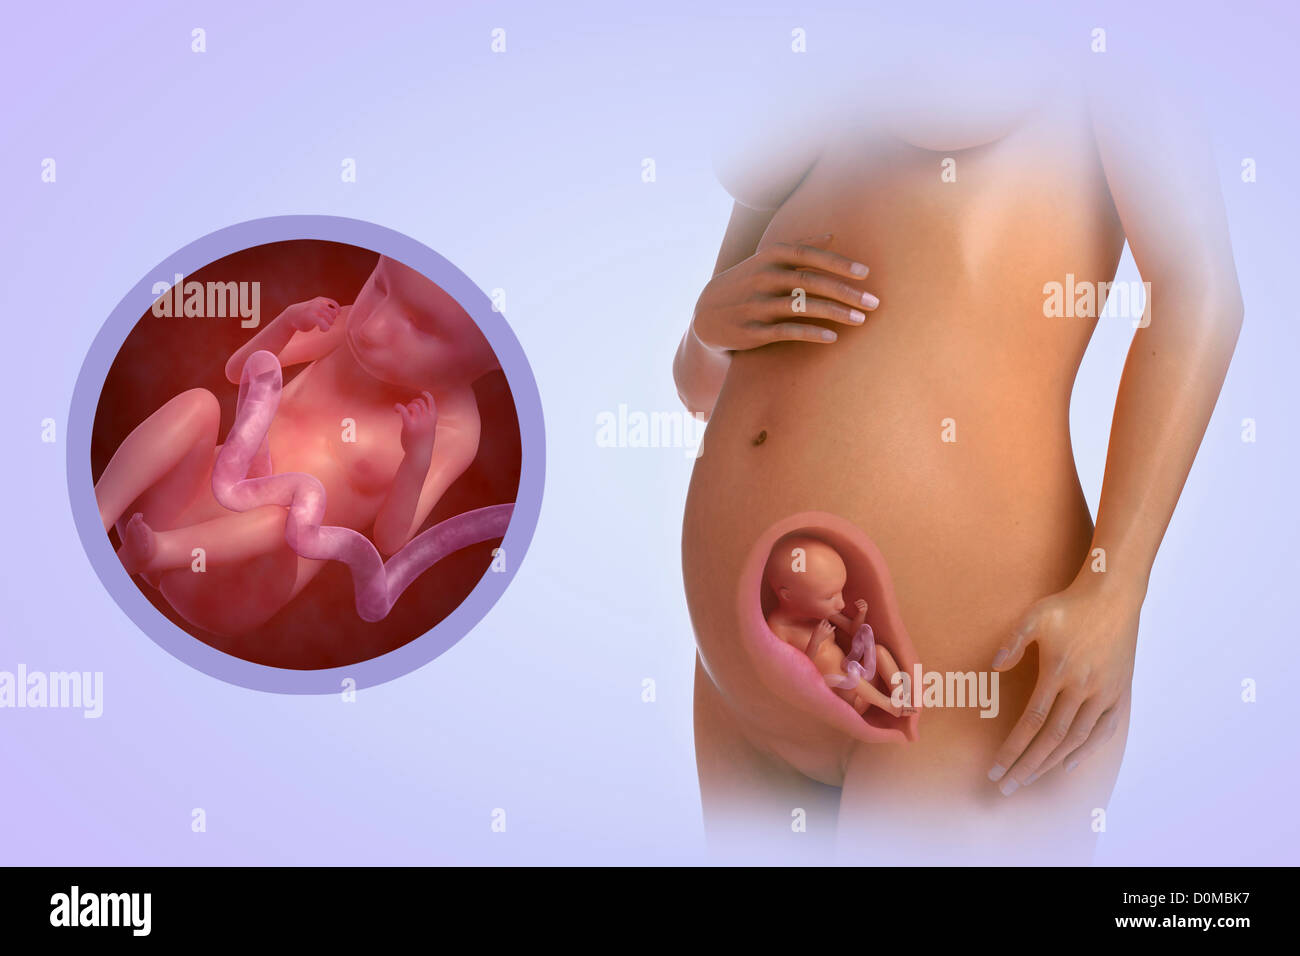

Illustrazione Di Una Donna In Stato Di Gravidanza E 22 Settimana Del Feto Foto Stock Alamy

Quali Cambiamenti Avvengono Nel Corpo Della Madre E Del Feto Alla Settimana 22